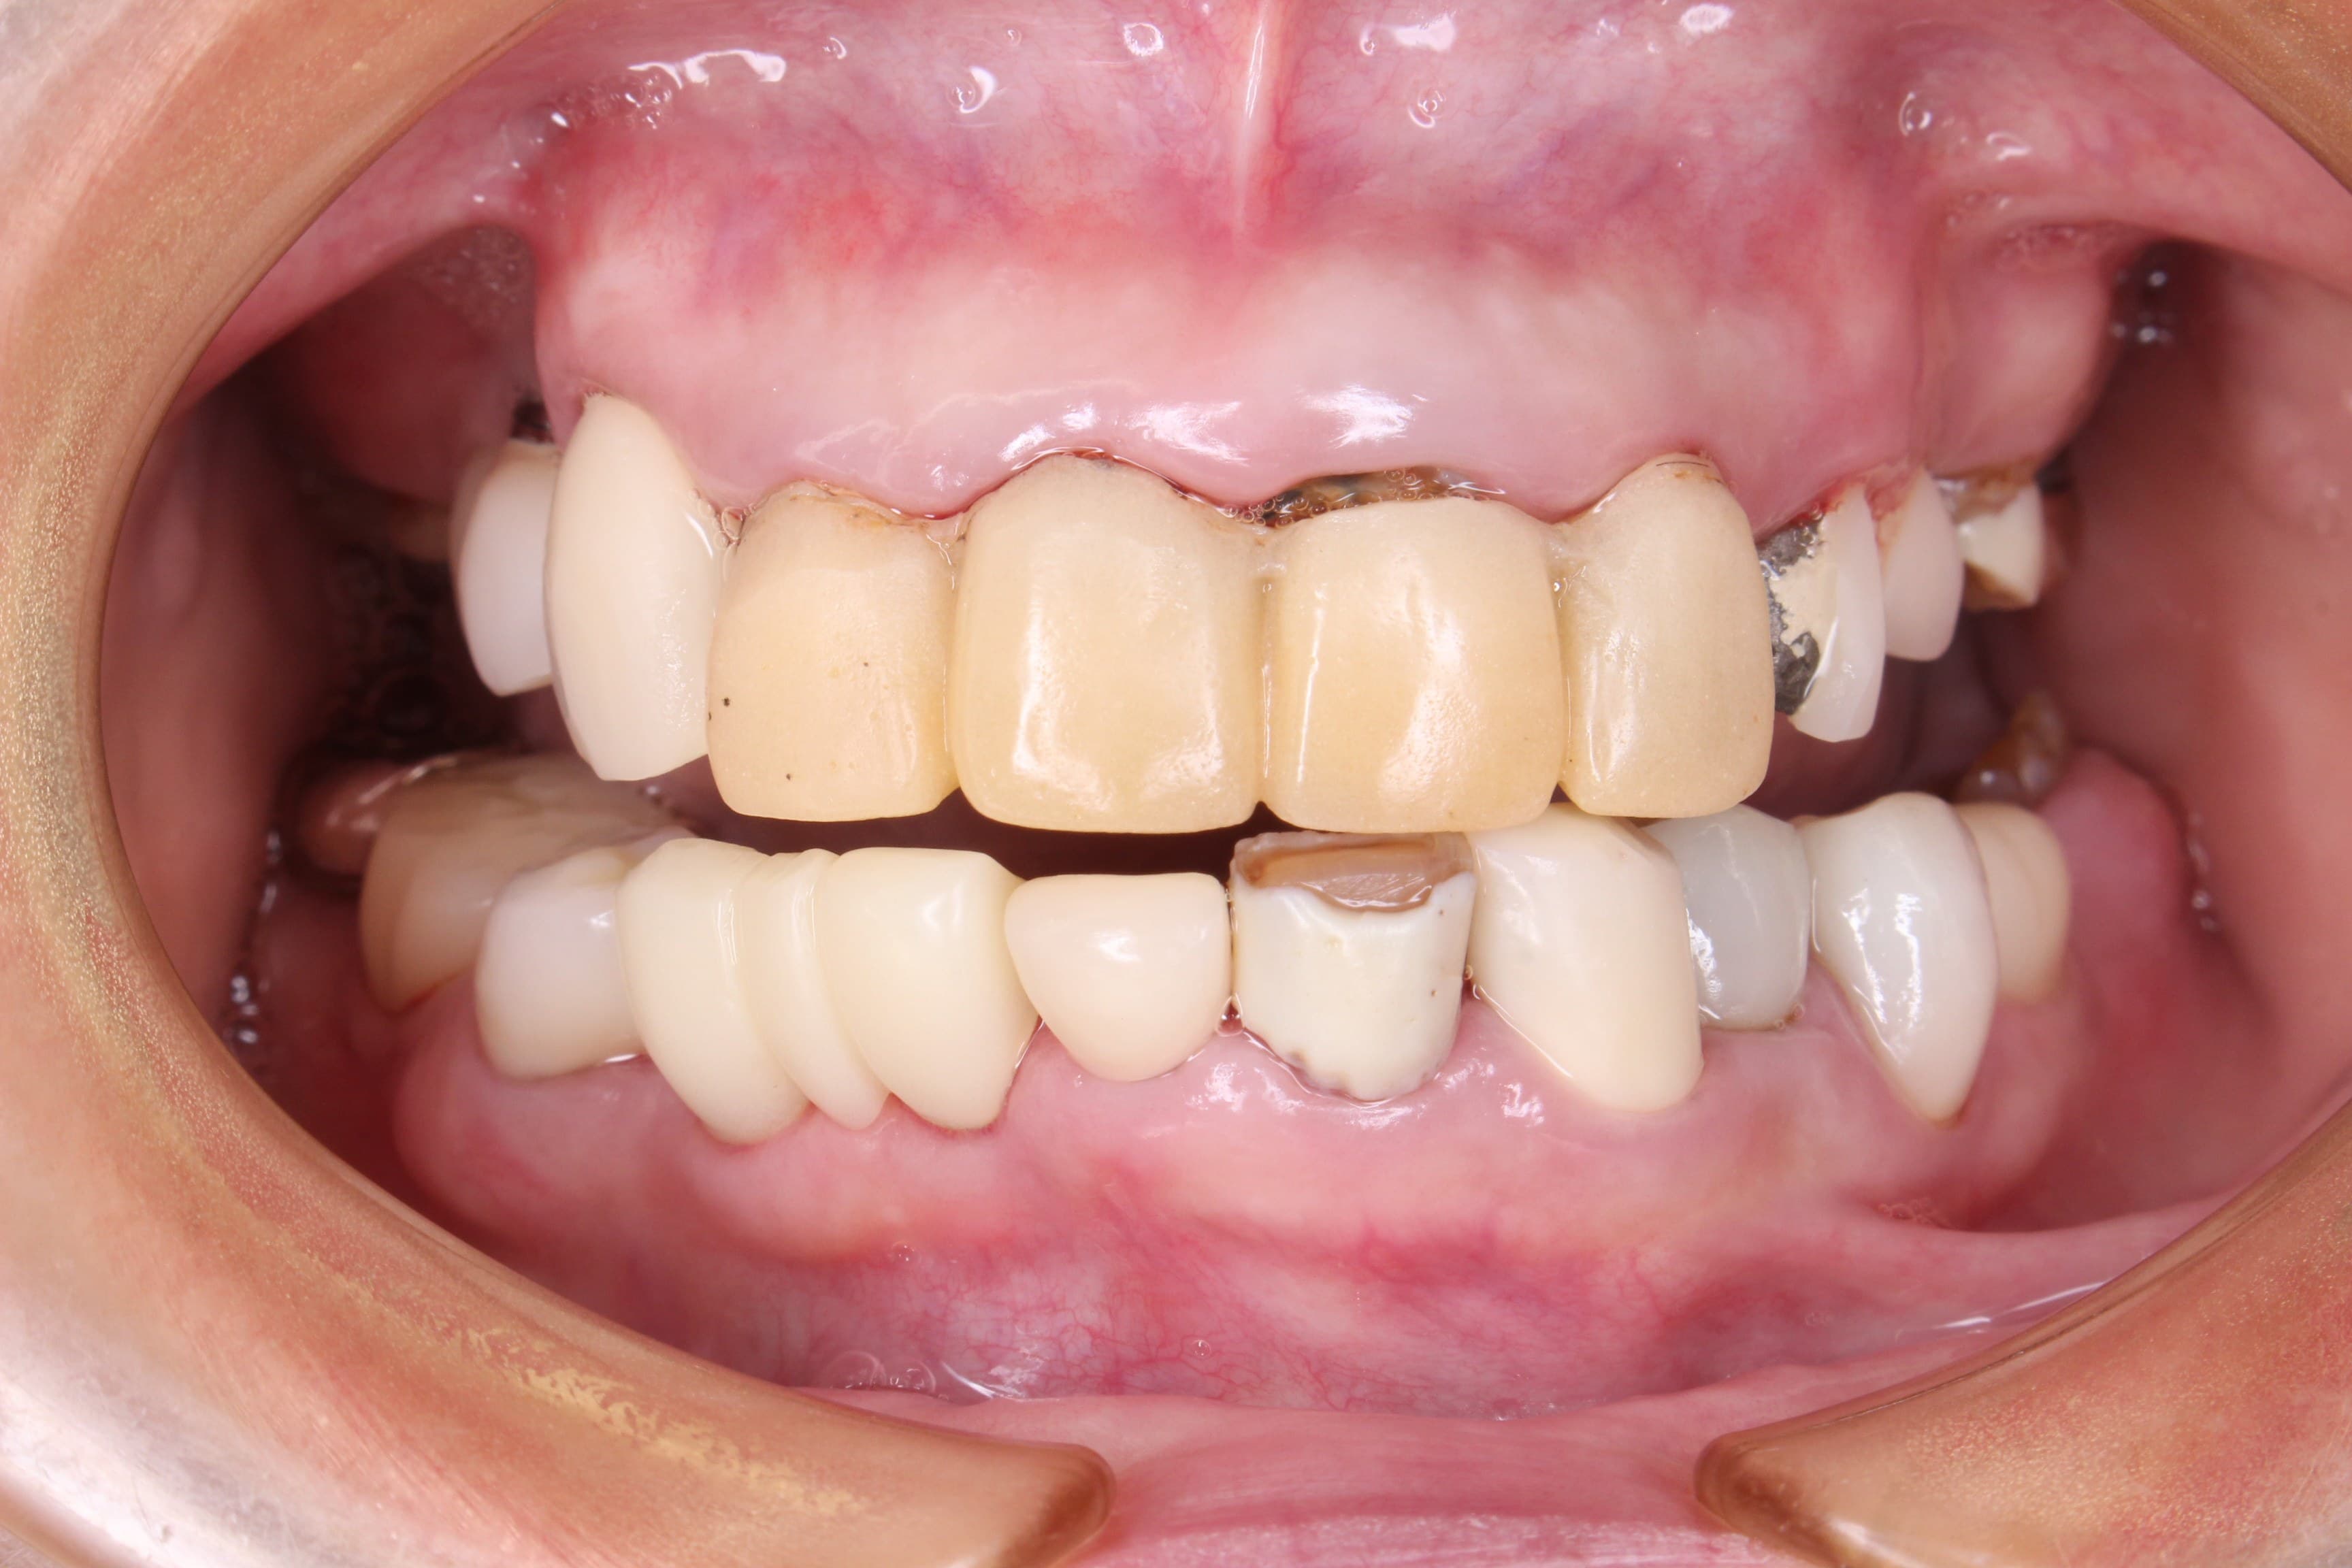

初診時 口腔内写真

全体的に炎症(発赤、腫脹、出血、排膿等)が広がっており、数年前に他院で入れたインプラント部の周辺歯肉も腫れ上がり、排膿していました。

ほぼ全ての歯に被せ物等の治療がしてあることからも、歯の治療で苦労してきたことが伺えます。